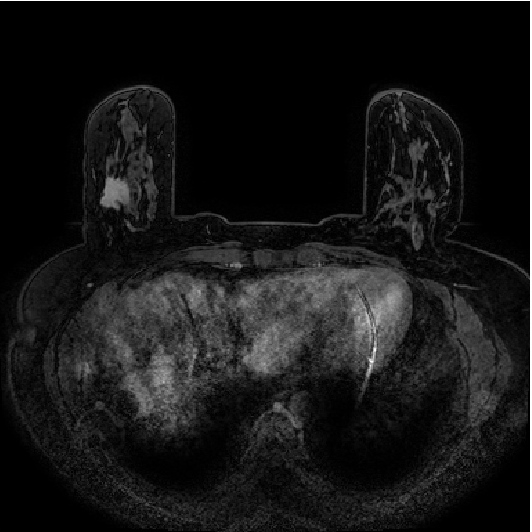

Assessment of the MTL method was performed on 1.5T and 3T DCE-MRI datasets of 447 and 193 breast lesions, respectively (Table 1). The DCE-MR images were acquired at the University of Chicago Medical Center over a span of 6 years from 2006 to 2012 on either 1.5T or 3T Philips scanners with T1-weighted spoiled gradient sequence. Each lesion was characterized as benign or malignant based on pathology from biopsy. Examples of 1.5T and 3T images of cancerous lesions are shown in Figure 1.